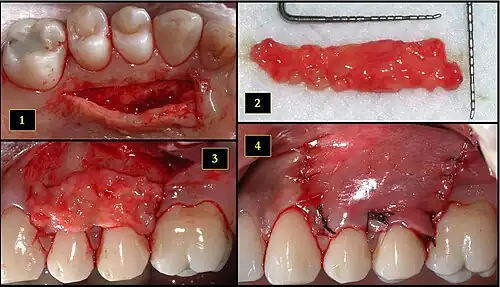

1. Ipsilateral palatal mucosa serving as the donor site

2. The retrieved connective tissue, approximately 25 × 6 mm in dimension

3. Connective tissue placed at recipient site

4. Recipient site flap coronally advanced and sutured to entirely cover the graft